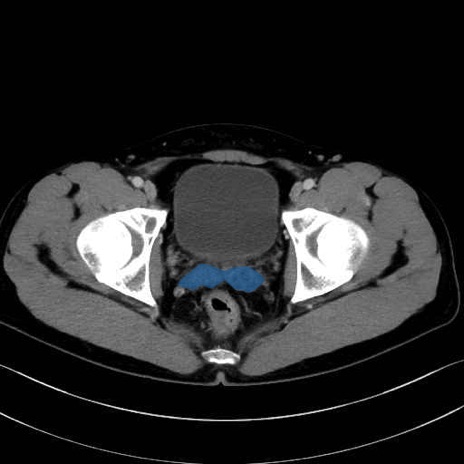

精嚢(seminal vesicle)のCT画像における解剖

症例

【症例】20歳代 男性 スクリーニング